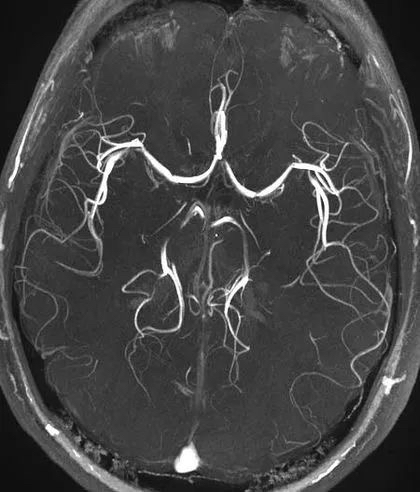

DSA:脑血管诊断的金标准,可显示动静脉以及血流动力学,并可三维成像。缺点是具有一定的有创性,价格较贵。

CTA:静脉注入造影剂后CT血管成像,显示动脉。显影比较精确。

MRA:无需注入造影通过核磁共振检查动脉血管和静脉。作为脑血管病筛查手段,内科常用。

血管成像分CTA,磁共振和DSA三种血管成像,这三种血管成像的主要作用是真真正正检测有没有动脉狭窄,并指导治疗方向。